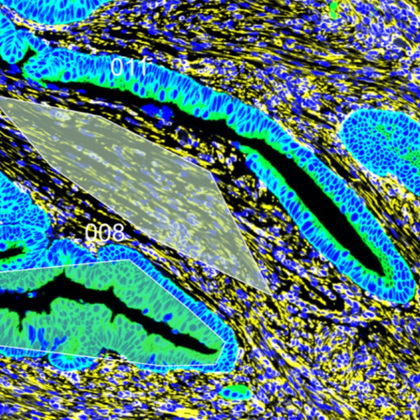

Spacia predicted the spatial distribution of the epithelial-mesenchymal transition (EMT) activating potentials of fibroblasts, endothelial cells, and B cells (top), the EMT signaling strength in prostate cancer cells (bottom left), and the lineage plasticity in prostate cancer cells (bottom right).

The researchers tested Spacia in a variety of contexts using data generated by SRTs, gathering significant insights. For example, using an SRT dataset from prostate cancer tissue, Spacia found that several cell types in the tumor microenvironment participate in a phenomenon called epithelial-mesenchymal transition, an important contributor to metastasis. Deploying Spacia on a pan-cancer SRT dataset that included breast, colon, skin, and lung cancers, among other types, the researchers found that B cells, a type of immune cell, react to signaling from tumor cells targeted by immunotherapy drugs known as checkpoint inhibitors. They also discovered a different CCC signature that accurately predicted cancer patient survival rates and their response to checkpoint inhibitors.